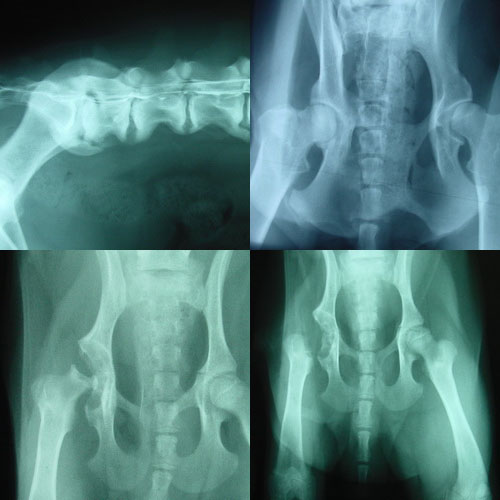

HD-Untersuchungsstelle (Zuchtuntersuchungen, ED,…)

Hüftgelenkoperationen